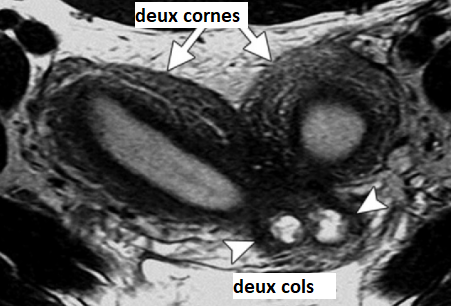

Utérus Didelphe